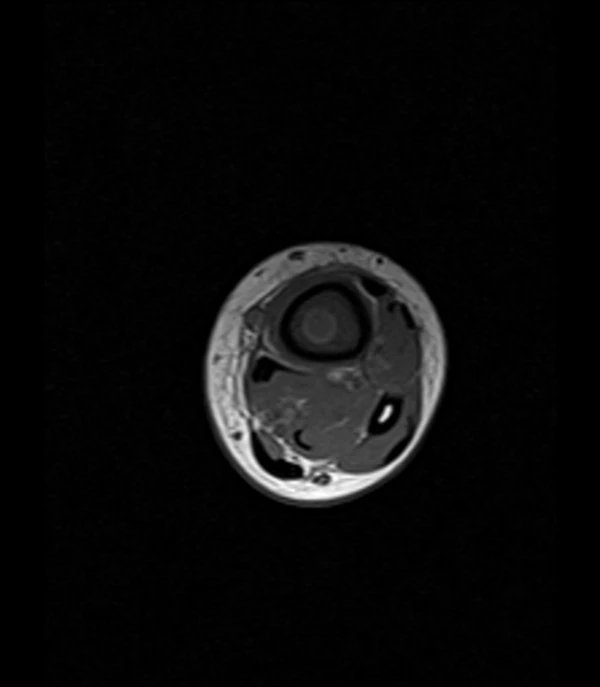

- Более точным методом инструментальной диагностики является МРТ. Абсцесс Броди описывается как «мишень» на МРТ, которая состоит их четырёх слоёв. Центральная часть представляет собой полость абсцесса. Внутреннее кольцо соответствует грануляционному слою, а внешнее — реактивному склерозу. Периферический венчик представляет собой отёка костного мозга. Кроме того, важен «признак полутени», который относится к переходной зоне с относительно высокой интенсивностью сигнала на Т1-взвешенных изображениях между абсцессом и реактивным склерозом[4].